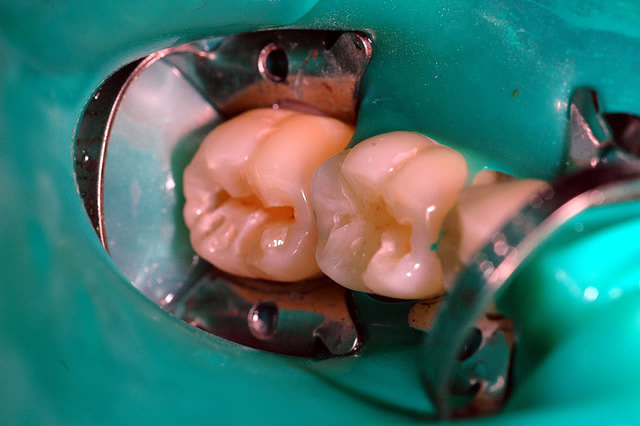

LE FIL DENTAIRE!!!VOUS N'AVEZ PAS PASSEZ LE FIL EN INTERDENTAIRE!!CA SERT A QUOI DE POSER UNE DIGUE??

Voila ce que m'a geulé mon prof qd j'ai fait comme toi l'autre jour...à bon entendeur...

Je m'associe aux remarques concernant l'étanchéité douteuse de la digue.

il existe:

- du fil dentaire pour passer les points de contacts

- de la digue liquide bisico (merci Carole) ou des mélanges bicarbonate-fixodent (et plein d'autre truc encore) pour les défauts périphérique d'étanchéité

Sinon les photos sont très belles, et les reconstitions plus belle qu'avec un "plombage" ;)